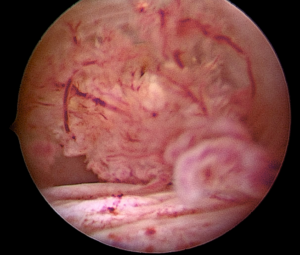

Operative hysteroscopy was conducted for diagnosis. This inpatient procedure required sedation. A vaginoscopic approach using a 30° optic lens from a Bettocchi set was employed and during the procedure, a 2 cm friable polypoid cervical lesion was identified and excised using a 5Fr grasper (See image 1 and 2). Histopathological examination indicated that the tumor comprised papillary excrescences lined by mucosecretory epithelium, supported by dense fibrous stroma with spindle-shaped and stellate fibroblasts. Immunohistochemistry for myogenin and desmin was negative.

Image 2

The macroscopic appearance of mullerian papilloma can easily be mistaken for malignant tumors, particularly vaginal rhabdomyosarcoma, due to its vascularized papillae that may resemble atypical vessels. Treatment involves excising the lesion.